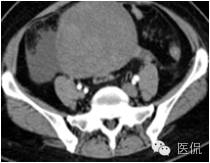

◆为单发肿瘤,表现为盆腔内实性肿块,囊性区较小;境界较清楚;肿瘤体积一般较大

◆CT表现:平扫呈等或稍低密度肿块,低于子宫肌层,可伴少量低密度囊变区,无壁结节

◆增强肿瘤实性成分呈轻-中度不均匀延迟强化,明显弱于子宫肌层;也可无强化